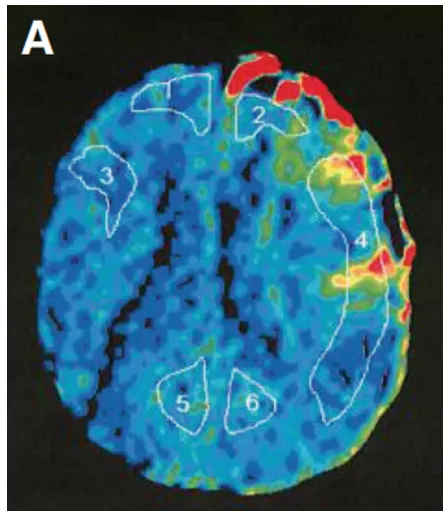

随后进行左侧STA-MCA搭桥术。术后不久观察到左MCA区域的高血流灌注现象(图3A),但未发生额外的缺血性和出血性并发症(图3B,C)。入院时神经功能缺损MRS评分为4分重度残疾,术后3个月时恢复2分轻度残疾,无需协助即可完成日常起居之事。

图3A:术后Xe-CT显示左侧大脑中动脉区域明显血流灌注(局部脑血流量:26.8 ml/100 g/min),血管通畅